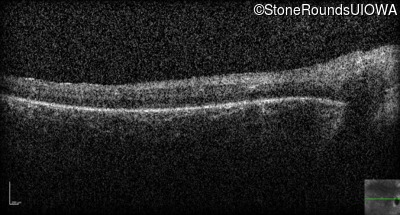

Optical Coherence Tomography - Right - Hand Motion 1' sc

Exemplar / OCT Stack